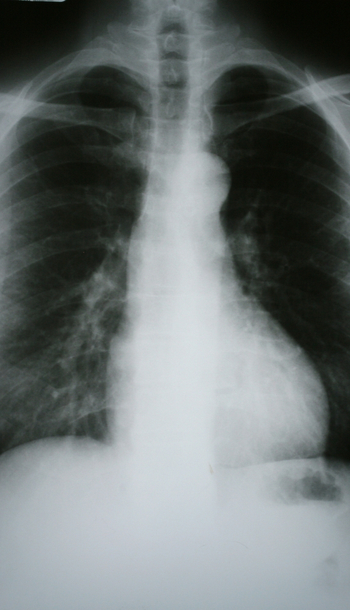

Plan de cuidados: EPOC

En el siguiente caso clínico sobre el Plan de cuidados del paciente con EPOC se mostrarán los cuidados de enfermería a seguir para mejorar y prevenir posibles complicaciones de salud de estos pacientes.